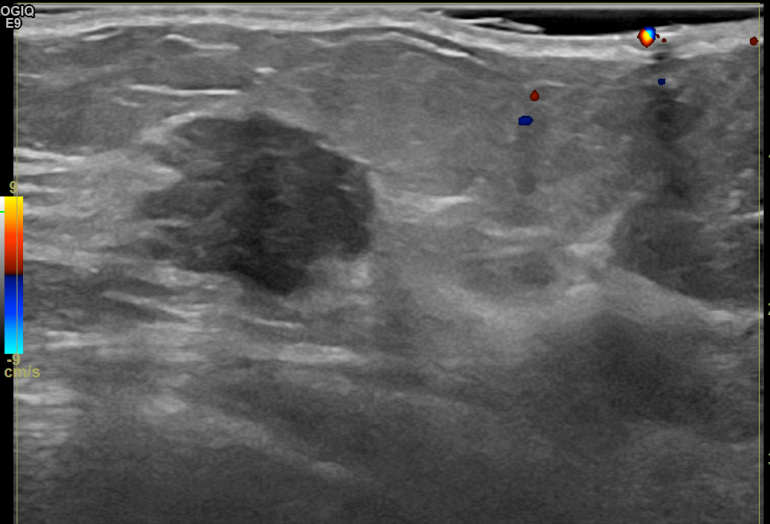

상기환자는 만져지는 멍울로 내원하신 60대후반 여성분으로 의심스러운 좌측혹

조직검사 시행해 침윤성암으로 진단되었습니다